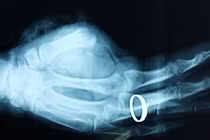

| 3 ngón tay được ngâm trong thùng đá lạnh. Ảnh: Người lao động. |

Tuy nhiên, thay vì phải bọc ngón tay bị đứt trong một túi nilon rồi mới đặt vào thùng nước đá thì người nhà bệnh nhân lại để ngâm trực tiếp các ngón tay vào đá lạnh. Bên cạnh đó, thời gian di chuyển từ nhà lên bệnh viện mất gần 9 tiếng nên các mô tế bào của ngón tay đã bị hoại tử, bác sĩ không thể khâu nối lại được.